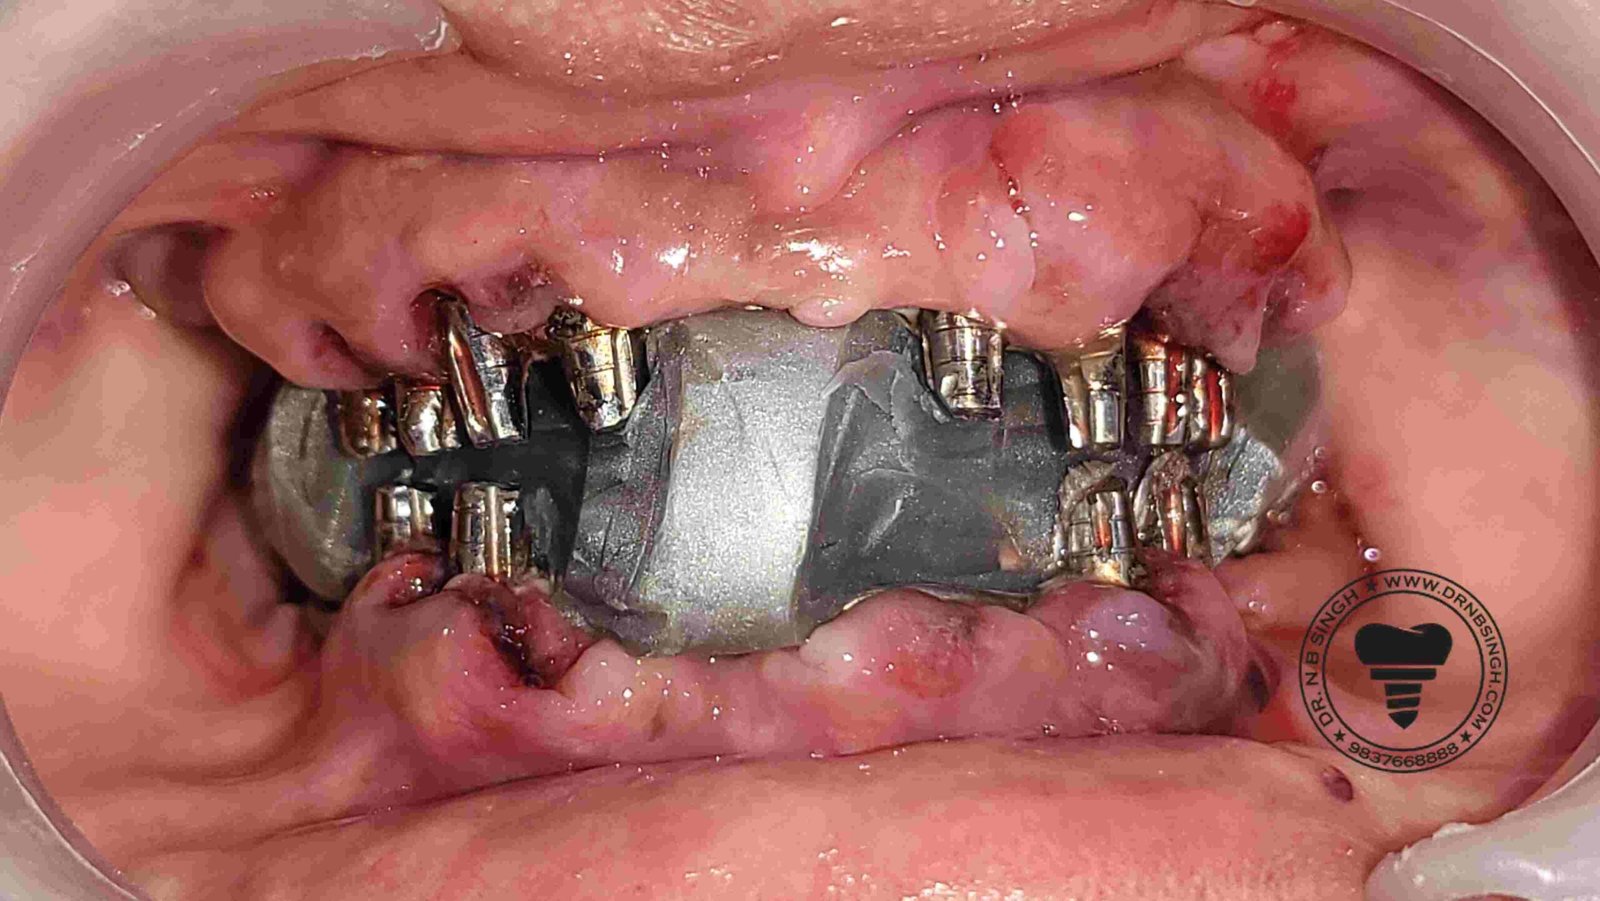

1002 Basal Full Mouth Implants Case Rubeena 2

1002 basal implant full mouth case rub 4